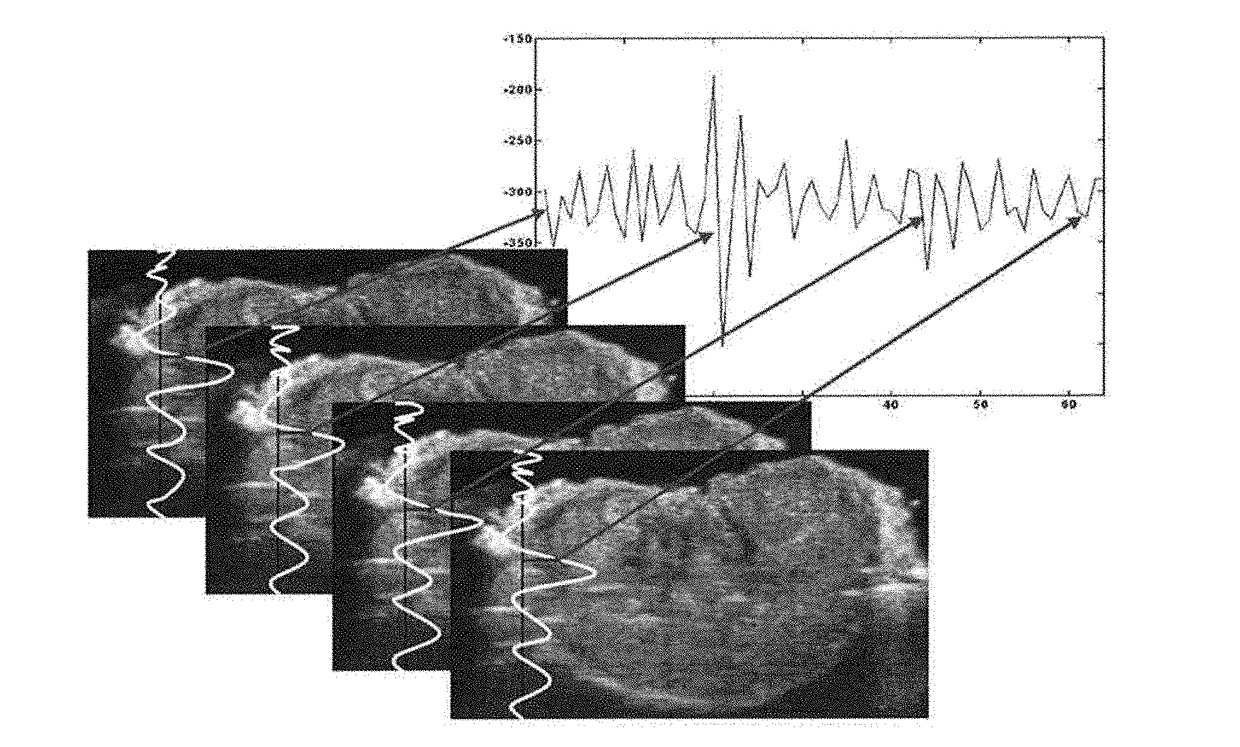

Method for Improved Ultrasonic Detection